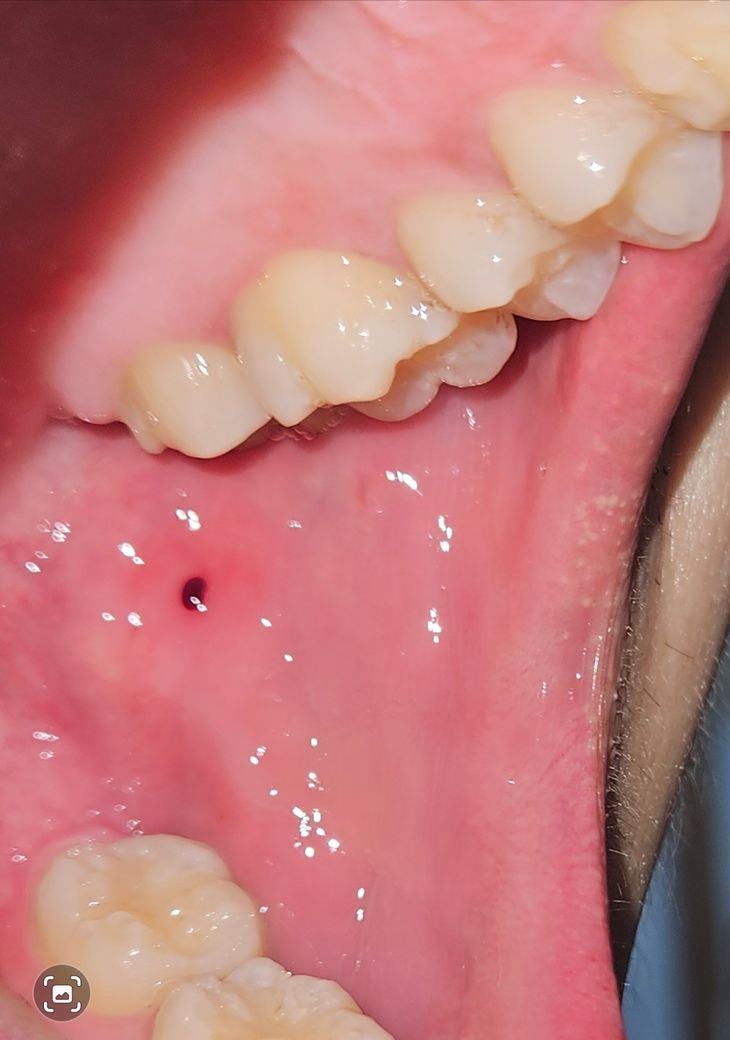

입안 볼쪽에 검은색 혈종이 생겼어요 구강암?

구강암일까요? 원래 피물집 생긴 곳이 항상 잘 씹히는 쪽입니다 반대쪽은 절대 안씹히는데 항상 씹히는 곳이 이번에는 피물집까지 생겼어요 ㅠㅠ

볼을 씹어서 혈종이 생긴 양상으로 보입니다. 구강암 등의 여부는 조직검사를 해봐야 정확히 알 수 있으나

사진상으로는 거리가 멀어보입니다.

• 안녕하세요 치과의사 김철진입니다. 사진에 보이는건 입술이 치아에 씹히면서 안쪽에 피가 고여서 그런겁니다. 터트리시면 괜찮습니다.

• 사진으로만 봤을 경우에는 혈액종으로 보입니다 혈액종은 구강 점막에 손상이 되었을 경우 출혈이 점막 안에 갇히면서 생기게 됩니다 마치 불집과 같은 것인데 크게 문제가 되지 않기 때문에 간단하게 제거할 수 있습니다 혈액종이 생겼다면 점막 조직의 과도하게 힘이 가해지고 있는 것이기 때문에 음식을 천천히 먹거나 치아에 가해지는 힘을 줄여주는 것이 좋습니다 자세한 확인을 위해서 치과에서 진료를 받아 보는 것을 권유 드립니다